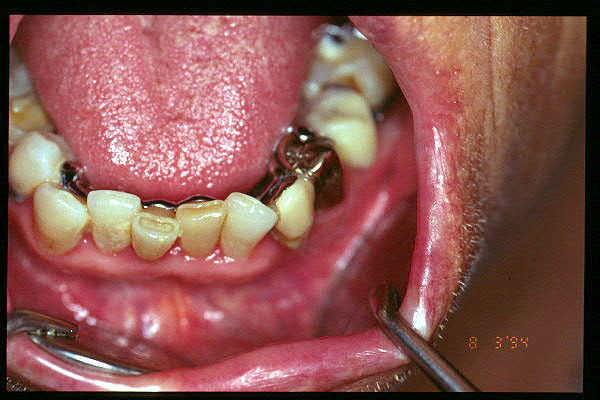

CM Extrusión de incisivos inferiores por falta de contactos oclusales